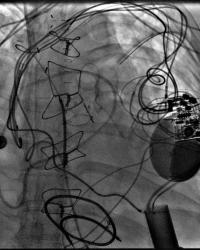

Figure - 01

CXR Sweet Spot™ Box Measurements |